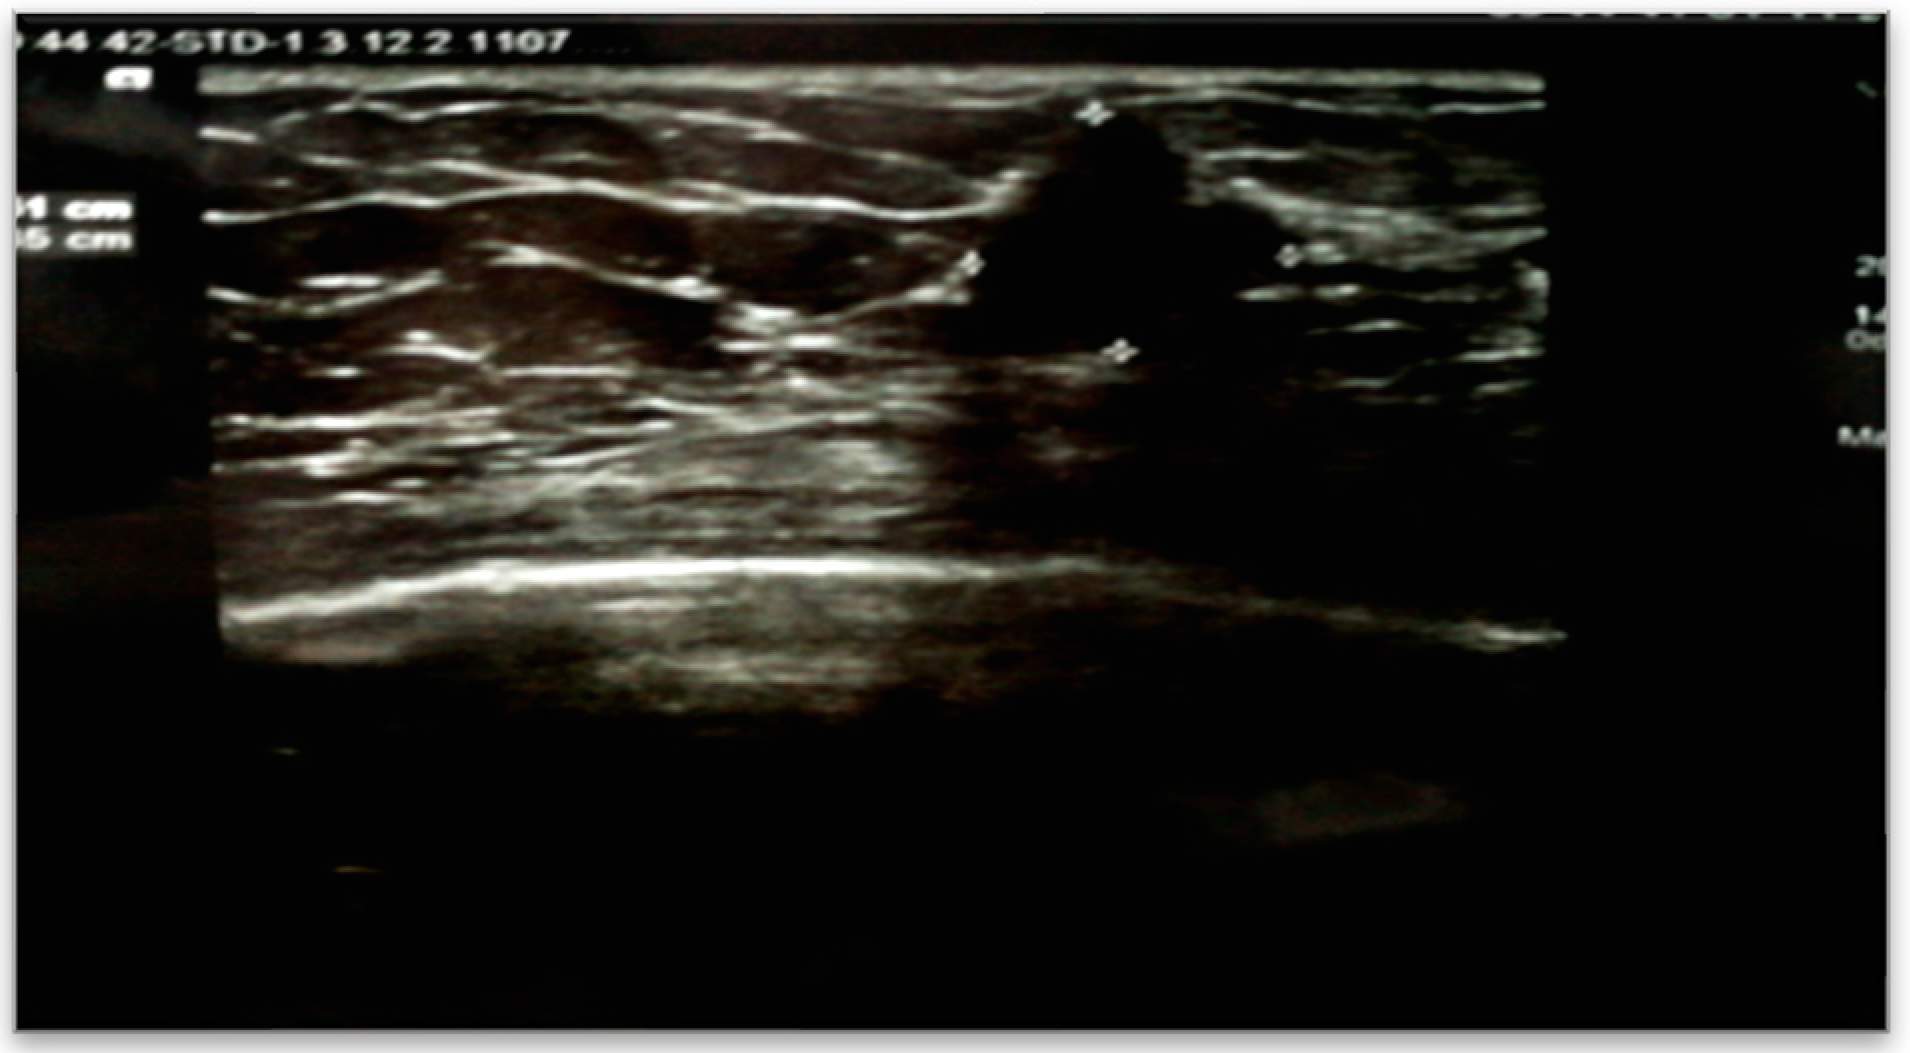

The patient underwent an abdominal CT examination, which described the presence of two accessory spleens measuring 24 mm and 19 mm, respectively, following pancreatectomy of the body and tail and splenectomy. Additionally, a left renal cystic mass measuring 28 mm was detected. Accidentally, a tumor in the right breast in the lower-outer quadrant was observed, measuring 14/15 mm. The high suspicion raised by the abdominal CT led to further imaging investigations, with breast ultrasound confirming the presence of a strongly hypoechoic spiculated mass measuring 16/13.5 mm, with irregular contours, as shown in Figure 1.

On ultrasound examination, mucinous carcinoma appears as a round or oval mass, isoechoic or hypoechoic compared to subcutaneous fat, often with posterior acoustic enhancement and internal echoes, along with cystic or solid components [30].

These imaging features have contributed to shaping the diagnosis in the case of our patient.

Figure 1. Right breast sonogram detected a hypoechoic mass about 16 x 13.5 mm.